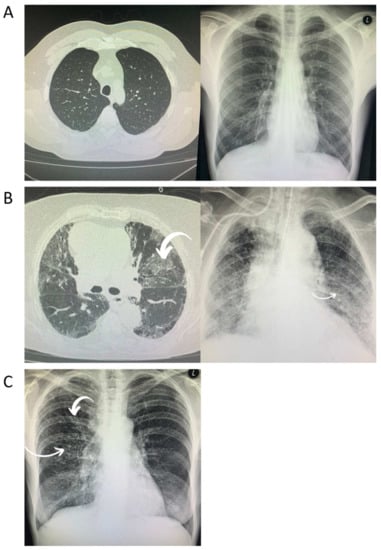

Bilateral consolidations that have a tendency toward the lungs’ periphery are usually found in CXRs and have an appearance that is most consistent with viral pneumonia. Chest CT images are most notable for showing bilateral and peripheral ground glass and consolidated opacities and are marked by an absence of concomitant pulmonary nodules, cavitation, adenopathy, or pleural effusions. These changes are considered typical for COVID-19 and may predict clinical deterioration [2] (Figure 1A–C). The rapid recognition of which stage the patient is at and the deployment of the appropriate therapy will have the greatest benefit [1]. However, it is likely that immunocompromised patients, such as those who are HIV-positive, will have the same presentation for opportunistic infections such as P. jirovecii. In addition, they may present with many other types of opportunistic lung infection, such as mycobacteriosis diseases, which may hinder differential diagnosis and the choice of treatment during the course of COVID-19. As a result, patients co-infected with SARS-CoV-2 and HIV might be at higher risk of unfavorable outcomes.

Figure 1. Radiological chest imaging of HIV-positive patients with COVID-19. (A) These images depict no radiological changes. (B) Typical radiological changes (bilateral and peripheral ground glass and consolidated opacities). (C) Atypical radiological changes (diffuse nodular changes).